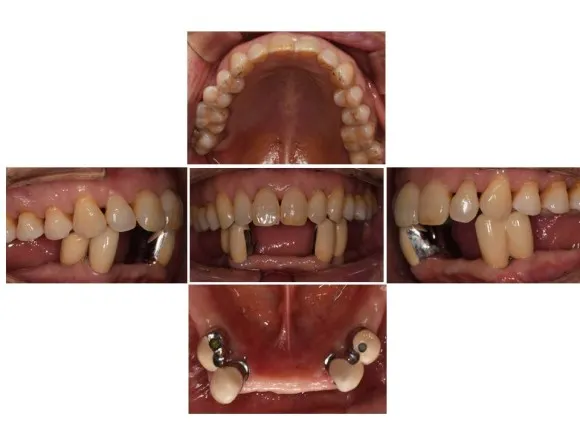

전후 사진으로 비교해보겠습니다.

부분틀니 장착 전